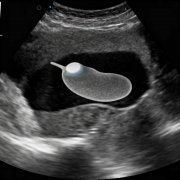

胆结石的形成是一个复杂的过程,可以形象地理解为胆汁中的某些成分过饱和后析出结晶,并逐渐聚集成石。 胆结石最主要的形成原因 胆结石根据成分主要分为两大类:... 全文>>

• 胆结石有什么症状?

胆结石是常见的胆道系统疾病,其症状表现多样,严重程度从无症状到危及生命不等,主要取决于结石的大... 全文>>